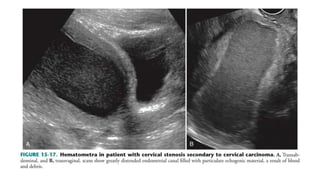

HYDROMETROCOLPOS AND

HEMATOMETROCOLPOS

• Obstruction of the genital tract results in the accumulation of

secretions and blood in the uterus(metro) and/or vagina (colpos),

with the location depending on the amount of obstruction.

• Before menstruation, the accumulation of secretions in the vagina

and uterus is referred to as hydrometrocolpos.

• After menstruation, hematometrocolpos results from the presence

of retained menstrual blood.

• Causes

Congenital

- imperforate hymen.

- vaginal septum

-vaginal atresia

-rudimentary uterine horn.

acquired

-cervical stenosis from endometrial or

cervical tumors

-postirradiation fibrosis